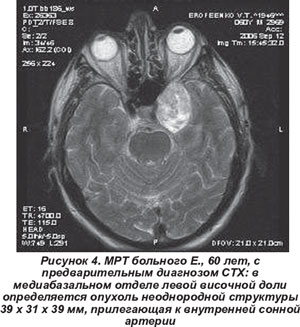

Опухоли чаще (у 8 чел.) развивались подостро без видимой причины. В клинической картине преобладали экзофтальм (22-28 мм), хемоз и тотальная офтальмоплегия у 7 больных. В 6 случаях причиной СТХ были первичные опухоли мозга (рис. 4). У четырех больных опухолевый процесс носил метастатический характер (первичный очаг обнаружен в легких, бронхах, предстательной железе, а также первичным очагом стала меланома кожи). У 4 пациентов произведено удаление опухоли (гистологически невринома - 2 чел., менингиома - 2 чел.). В 1 случае для лечения использован gamma knaif.